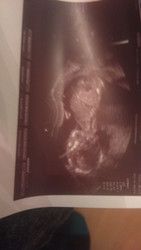

Kleines Update von mir. Ich hatte gestern nun auch meinen ersten richtigen Termin. Der letze war ja etwas unentspannt wegen den Blutungen und so. Aber jetzt ist wirklich alles super. Bin auch noch mal nach vorne gerutscht mein Termin ist wohl der 9.Mai und ich bin somit jetzt bei 10 + 4.

Auf dem Ultraschall hatte man das Gefühl schon ein richtiges Baby sehen zu können. Verrückt wenn man überlegt wie klein dieser knirps da drinnen noch ist. Hat einen Purzelbaum gemacht. Ich finde das klingt unfassbar. Ist doch noch so mini alles. So langsam wird es immer realistischer :)